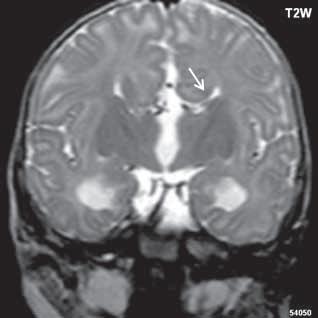

Roztroušená skleróza (RS) 189

II 1 1